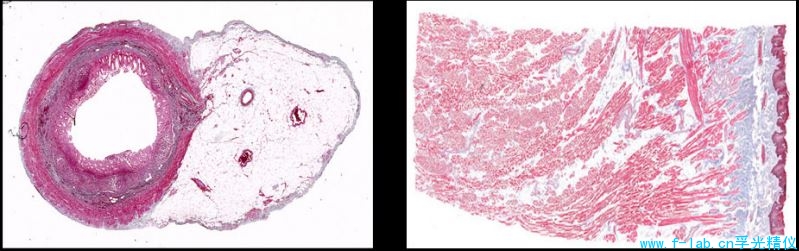

病理切片扫描仪能够以超高分辨率,丰富的对比度和真实的彩色对整个病理切片标本成像,扫描面积高达36.14mm x 21.59mm,有效图像高达10.248x 6.12像素。

传统显微镜装配低功率物镜和数字相机,不能获取大于6mm直径的标本图像,这台病理标本扫描仪可扫描高达36mm 直径样品图像。

而这套病理切片扫描仪能够以超高分辨率,丰富的对比度和真实的彩色对整个病理切片标本成像,

扫描面积高达36.14mm x 21.59mm,有效图像高达10.248x 6.12像素。